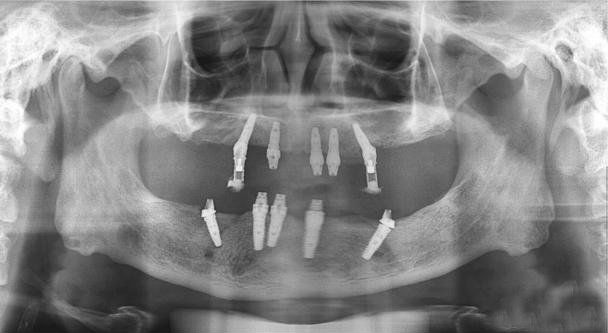

下颌拔牙3个月后,虽骨密度较低,但已经达到种植标准,在左下3、6、及右下3辅以人工植骨,并在左下3、4、6、7及右下3、4、6、7同期植入8颗种植体,

三个月后,朱先生来院复查,种植体与骨结合良好,无任何金属过敏反应及副作用,连接愈合基台。